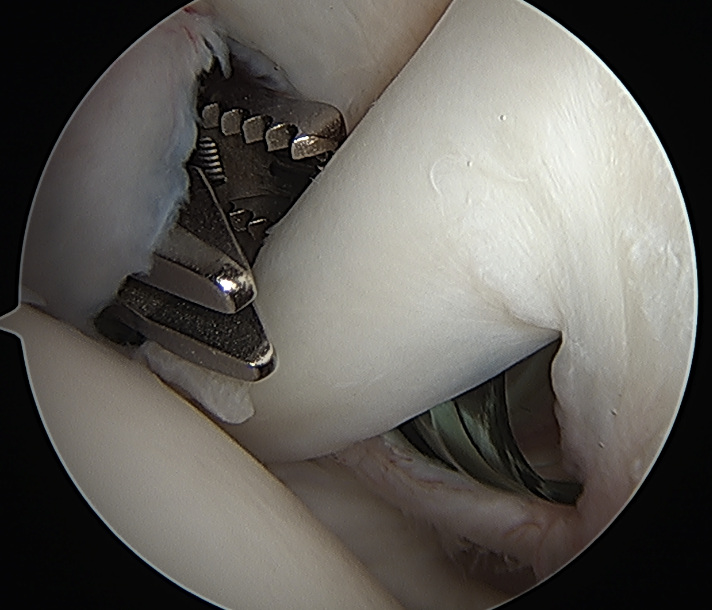

Arthroscopic suprapectoral biceps tenodesis

Technique

- tag biceps tendon with high strength suture and release

- repair superior labrum with one or two anchors

- anchor biceps tendon into bicipital groove

Portal just anterior to supraspinatus tendon

Tag biceps and release

Anchor biceps tendon into bicipital groove